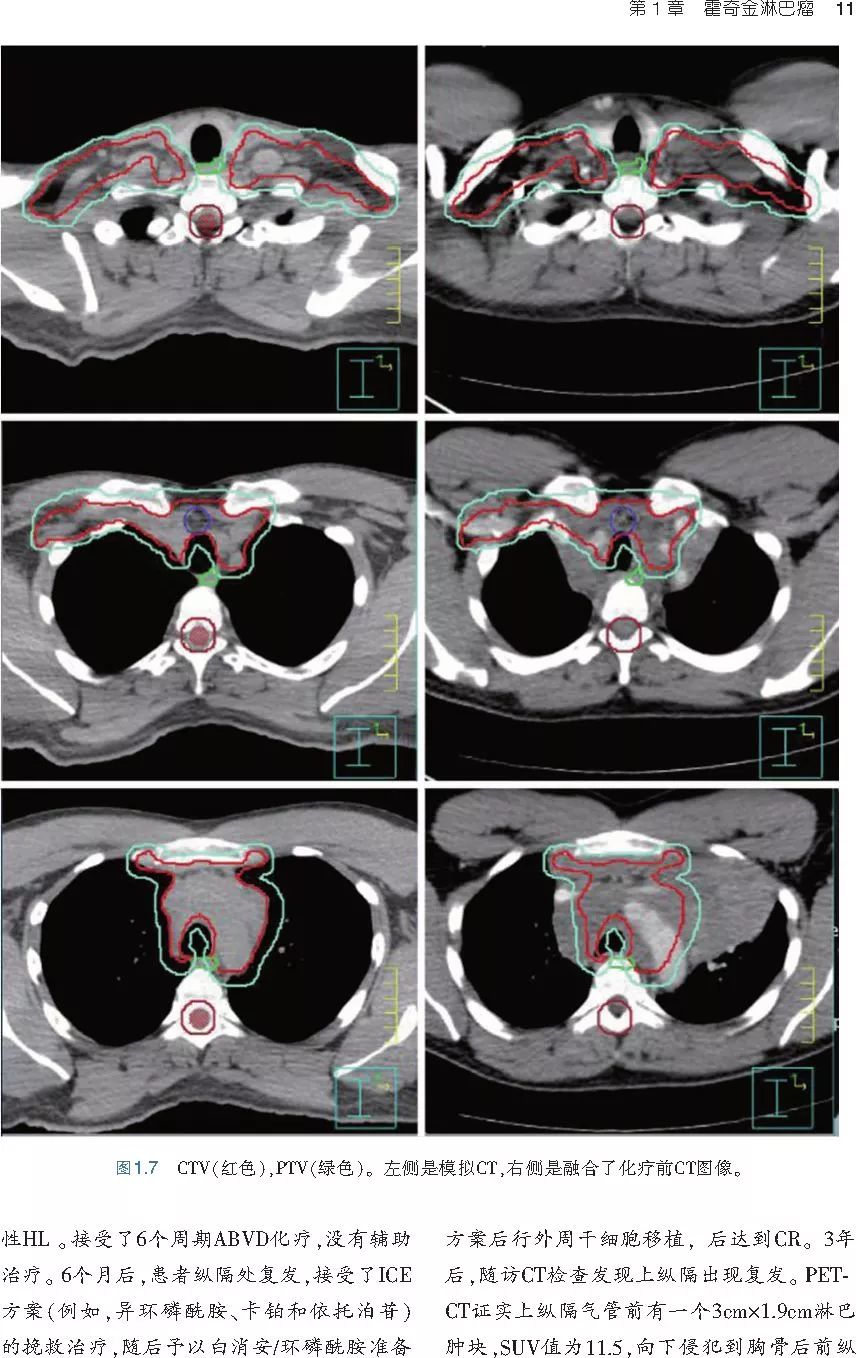

❤ 展开疾病诊断、病理描述及治疗方向的详细阐述,包含医学影像,图文并茂,深入浅出。

本书旨在帮助临床医生对常见血液系统恶性肿瘤疑难病例进行管理,包括霍奇金淋巴瘤、非霍奇金淋巴瘤和白血病患者,并通过多个病例进行阐述。案例讨论遵循标准格式,包括临床描述,其次是与诊断相关的病理描述和分期,然后详细讨论治疗选择。最后,确定治疗方案,并提供所使用的规划放疗技术/方式的图像。对放射肿瘤医生进行临床决策非常有帮助,对于血液病临床医生也有很好的指导作用。

近年来,放射治疗技术得到了迅速发展,调强放疗、图像引导放疗及其他新技术方法等,对恶性肿瘤治疗产生了巨大影响。现代放疗技术使精确定位、靶区勾画及给量成为可能,实现了肿瘤局控率和生活质量的双赢,对血液系统恶性肿瘤的临床治疗也产生了一定的影响。此书内容上不仅反映了血液系统恶性肿瘤综合治疗的进步,更是对其中放射治疗的新变化进行了系统、详细的阐述,这对当前血液系统恶性肿瘤放射治疗临床实践具有非常好的指导作用和参考价值。